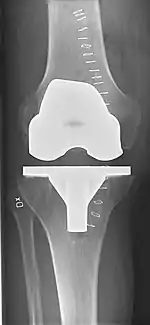

Knee replacement surgery can be performed as a partial or a total knee replacement.[2] In general, the surgery consists of replacing the diseased or damaged joint surfaces of the knee with metal and plastic components shaped to allow continued motion of the knee.

Technique

The surgery involves exposure of the front of the knee, with detachment of part of the quadriceps muscle (vastus medialis) from the patella. The patella is displaced to one side of the joint, allowing exposure of the distal end of the femur and the proximal end of the tibia. The ends of these bones are then accurately cut to shape using cutting guides oriented to the long axis of the bones. The cartilages and the anterior cruciate ligament are removed; the posterior cruciate ligament may also be removed but the tibial and fibular collateral ligaments are preserved.[15] Whether the posterior cruciate ligament is removed or preserved depends on the type of implant used, although there appears to be no clear difference in knee function or range of motion favouring either approach.[16] Metal components are then impacted onto the bone or fixed using polymethylmethacrylate (PMMA) cement. Alternative techniques exist that affix the implant without cement. These cement-less techniques may involve osseointegration, including porous metal prostheses. Finally, stability and range of motion is checked, followed by irrigation, hemostasis, placement of hemovacs, and closure.[17]

Femoral replacement

A round ended implant is used for the femur, mimicking the natural shape of the joint. On the tibia the component is flat, although it sometimes has a stem which goes down inside the bone for further stability. A flattened or slightly dished high-density polyethylene surface is then inserted onto the tibial component so that the weight is transferred metal to plastic not metal to metal. During the operation any deformities must be corrected, and the ligaments balanced so that the knee has a good range of movement and is stable and aligned. In some cases the articular surface of the patella is also removed and replaced by a polyethylene button cemented to the posterior surface of the patella. In other cases, the patella is replaced unaltered.